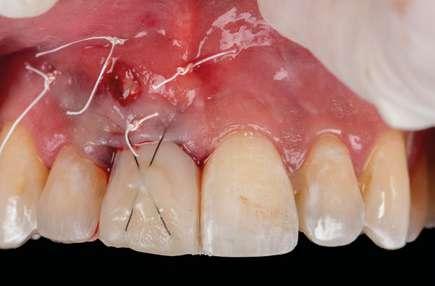

na paciente de 35 años (Figura 1) fue remitida a la Clínica de Odontología Reconstructiva de la Universidad de Zúrich debido a una infección crónica en el diente 11 y con expectativas estéticas muy altas. El diente 11 había sufrido un trauma hace 10 años y había sido tratado con multiple endodoncias sin éxito. El diente presentaba un absceso bucal (Figura 2), una bolsa periodontal aislado de 9 mm, y una ausencia de la tabla vestibular ósea (Figura 3). El diagnóstico se estableció como una fractura radicular vertical, lo que resultó en un pronóstico pobre. El plan de tratamiento consistió en una extracción combinada con preservación alveolar, colocación de implante diferido con injerto de tejido conectivo, una corona cerámica implantosoportada en 11 y una nueva carilla de cerámica para el diente 21.

El diente 11 fue extraído (Figura 4), seguido por la preservación alveolar. Se realizó un injerto pediculado de espesor parcial rotado del paladar (Figura 5), junto con una membrana de colágeno reabsorbible, un xeno-injerto bovino y cianoacrilato sellando al alveolo (Figura 6). La provisionalización consistió en un puente adhesivo de resina con dos alas de metal. El alveolo se dejó cicatrizar durante 6 meses, después de los cuales se tomó una impresión digital así como un escáner CBCT (Figura 7). Se llevó